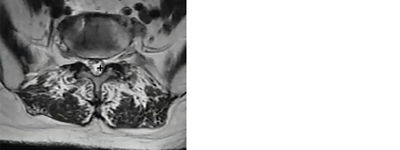

Identifying anatomical landmarks in a mild® patient

Photo Courtesy of James Lynch, PA – L3/L4 interspace

By moving our image up to L2-L3, we can see an excellent comparison of the healthy central canal. The large white area shows that at this level, the thin black ligament is not compressing the nerves.